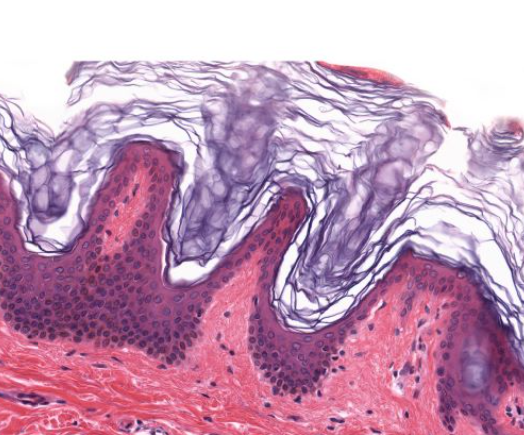

Keratinized Stratified Squamous Epithelial Tissue